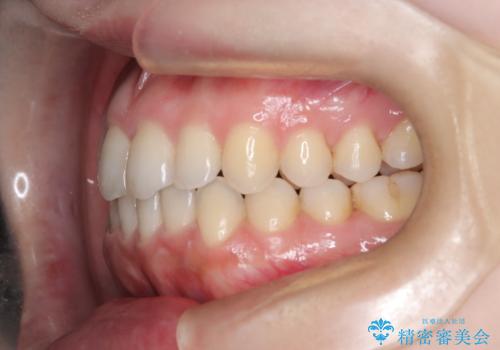

【オープンバイト】前歯のがたがたをなおしたい。

- 笑った時の前歯の見た目が気になることを主訴に来院されました。

上の歯が下の前歯を少し隠すぐらいを目指し、インビザラインにて治療を行いました。

オープンバイトの後戻りを防ぐためには舌のトレーニングが必要です。